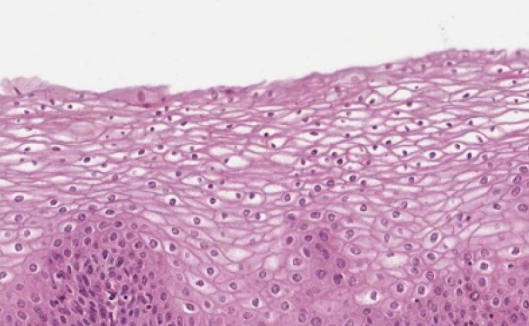

The type of epithelium indicated by the arrows in the image below is…?

..stratified squamous.

What function is the type of epithelium represented in the image below specialized for?

Resisting wear and tear

Stratified squamous epithelium

Transcellular transport: Simple squamous epithelium

Both secretion and absorption: simple cuboidal and simple columnar